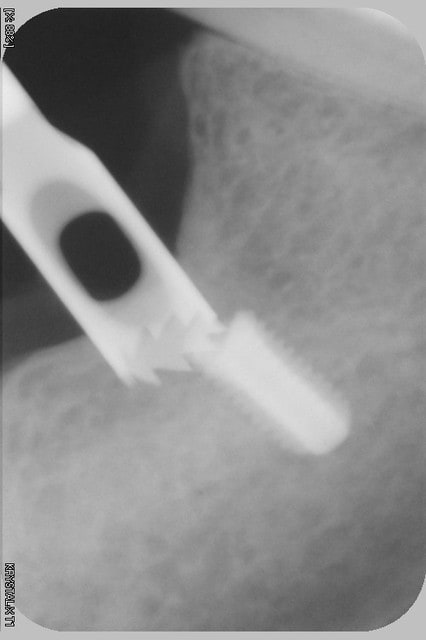

l'irrigation interne moi je n'en veux plus...c'est un nid à merde in-nettoyable correctement, et quelque part au patient suivant, tu lui ré-injectes toute ce bouillon de culture directement dans l'os....

çà t'évite peut être quelques problèmes d'échauffement...mais pas vraiment les infectieux...

çà me fait penser...irrigation interne...Zimmer??? (il me semble une des dernières marques à proposer ce genre de forets...qui coûtent la peau du cul, donc on les garde jusqu'au bout...pas bon, car un foret qui ne coupe plus, çà chauffe fort...il vaut mieux un foret classique qui coupe bien utilisé à basse vitesse...)

Pour l'irrigation interne, je n'en parlerai même pas tellement le concept me semble dépassé.

Juste pour le plaisir, après stérilisation passe un fil métal dans ton foret et confirme que tu ne trouve que le fil à la sortie...